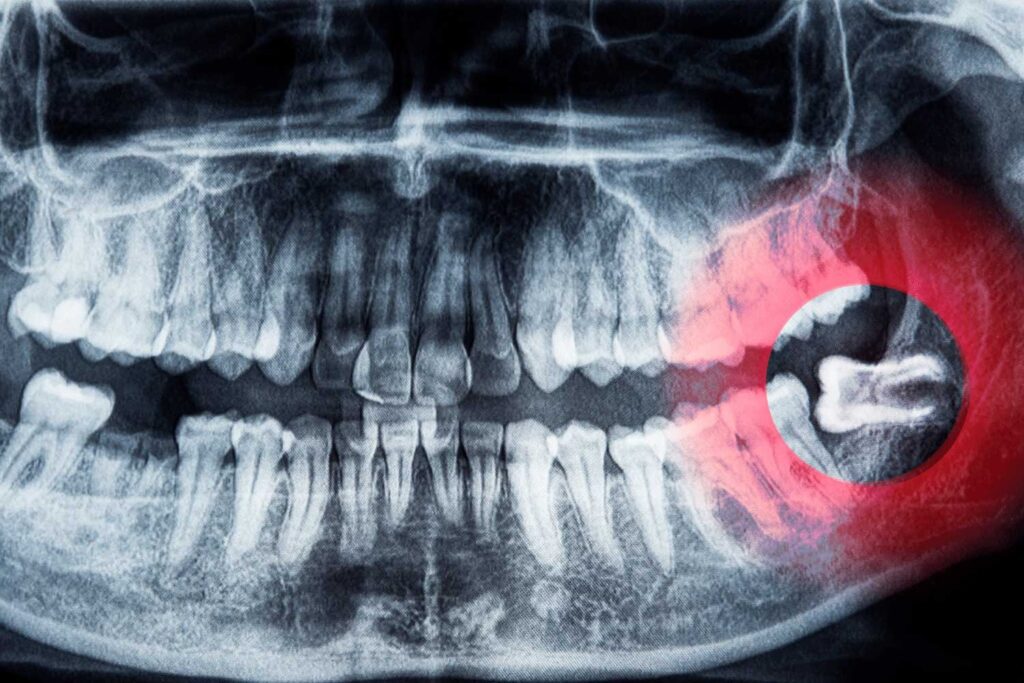

Extração de Siso Sem Dor em Alphaville Barueri?

A Extração de Siso ou Dente do Juízo não precisa ser um procedimento doloroso ou complicado! Na Armoni Odontologia Estética, utilizamos tecnologia de ponta e técnicas minimamente invasivas para garantir uma experiência confortável, segura e com recuperação rápida.

Você sabia que a falta de cuidados adequados durante e após a cirurgia do siso pode causar complicações graves, como infecções severas e, em casos extremos, até mesmo riscos fatais? Por isso, é essencial priorizar a esterilização rigorosa e buscar tratamentos que promovam uma recuperação segura e eficaz.

Durante a extração do siso, a esterilização dos instrumentos cirúrgicos é fundamental para evitar que bactérias entrem na corrente sanguínea ou infectem os tecidos ao redor. Sem esses cuidados, um procedimento simples pode levar a: